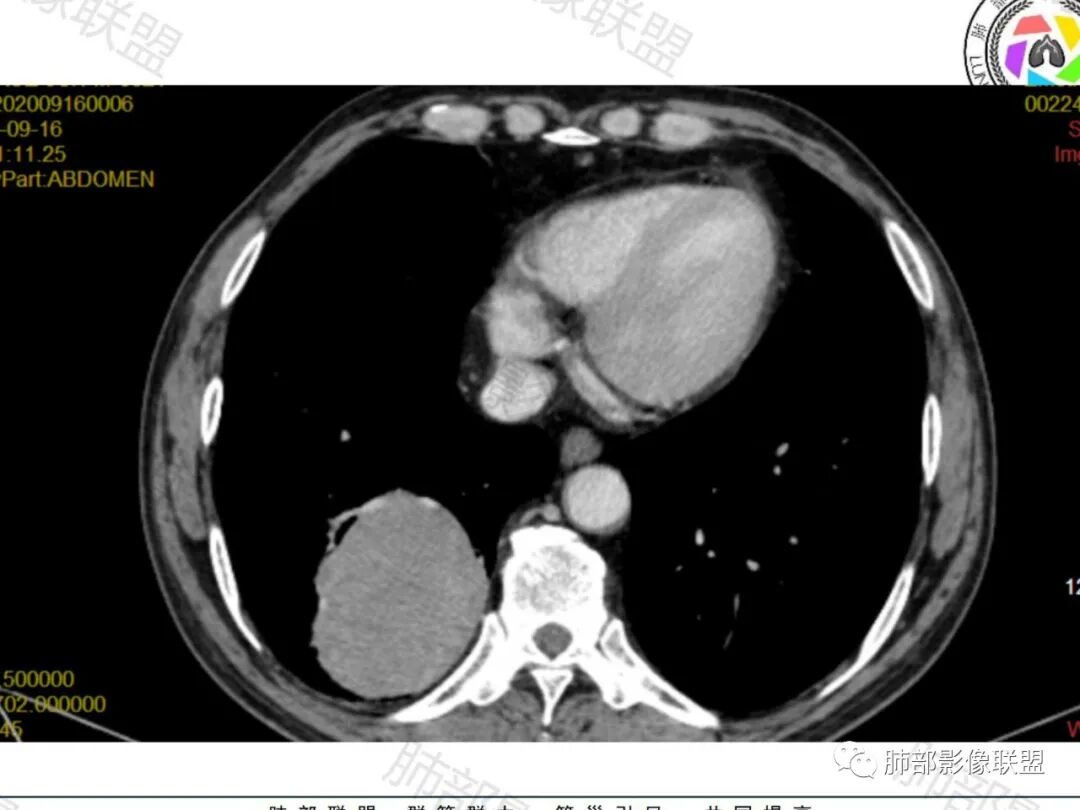

右肺下叶一类圆形肿块影,内缘边缘光滑,外缘边界模糊,可见磨玻璃影,整体以彭隆为主,部分边缘包绕支气管,平扫密度尚均匀,增强后不均匀强化,部分与膈肌黏连,临床,62岁男性,无症状,考虑恶性:腺癌,鳞癌,神经内分泌癌,肉瘤

老年人,偶然发现,右肺下叶类圆形软组织占位,密度较均匀,病灶边缘光滑,无毛刺分叶,支气管血管受挤压向外移位,增强病灶强化较均匀。考虑恶性肿瘤,外向内生长,肉瘤,肉瘤样癌,癌肉瘤,其次神经内分泌癌。

老年男性,右肺下叶软组织肿物,整体外形光整,周围组织推挤,可见血管贴边,貌似又有血管进入,整体强化均匀,考虑良性可能大,硬化性肺细胞瘤?鉴别sft

老年男性,偶然发现,说明平时没有症状,边缘光整,血管贴边,整体强化均匀,倾向于良性或者低度恶性(PSP?类癌?)

老年男性,肿瘤标志物高,右肺占位,边界清楚,内部密度均匀,坏死不明显,无明显分叶,血管贴边,考虑PSP,老年男性,肿块大,需鉴别恶性,肉瘤样癌?高分化鳞癌?

男性,62,胆结石入院胸部CT偶然发现占位。肿标稍增高,右肺下叶胸膜下肿块,边缘尚清,密度较均匀,增强明显强化,血管贴边,空气新月征?静脉期可见低强化区,首先考虑PSP,鉴别肉瘤样癌及神经内分泌肿瘤

老年男性,右肺下叶肿块,边缘光整,血管贴边,部分血管进入,整体强化尚均匀,考虑大细胞癌,鉴别PSP、SFT

右肺下叶类圆形软组织肿块,病灶边缘光滑,无明显毛刺分叶,支气管受压推移,血管贴边,部分血管进入病灶,增强病灶强化不均匀,内可见低密度,病灶与右侧膈肌分界不清,考虑神经内分泌肿瘤,大细胞癌。鉴别PSP

老年男性,肿瘤标志物高,右肺下叶类圆形肿块,宽基底与胸膜相连,边缘光整,密度均匀,周围气管及血管受压推移,延迟强化,其内见纤细血管,似有小低密度灶,首先考虑间叶组织恶性肿瘤,良性平滑肌瘤、纤维瘤不除外

患者中老年男性,检查发现右下肺占位。查肺癌标记物稍有升高。血常规白细胞计数稍降低。胸部CT:右肺下叶后基底段类圆形肿块,边缘光滑,边界清楚,周边见气管受压扩张,增强轻度强化,内见点状低密度影,见血管贴边。综合考虑良性过低度恶性病变,PSP可能,其它恶性肿瘤待排。

支气管,血管均受压推移,类圆形占位,无分叶,无毛刺,光滑表面,明显均匀强化,倾向于psp,鉴别错构瘤,肉瘤,肉瘤样癌,类癌等神经内分泌肿瘤,转移,imt。

老年男性,右肺下叶软组织肿块,边缘光滑,血管和支气管贴边,肿块与膈肌分界不清,增强后不均匀强化,可见点片状低密度影,考虑良性或低度恶性肿瘤,psp,神经内分泌肿瘤

右肺下叶大肿块,血管贴边,部分小分支进入肿块内,密度略欠均匀,边缘总体光滑,支气管关系不明确,老年人,总体考虑恶性,nse高,首先考虑神经内分泌癌,鉴别肉瘤,转移瘤

右下肺大团块,边界较清,病灶内有血管影,小灶低密度,胸膜下脂肪清晰,需要薄层确定肺血管有没穿行,疾病谱:神经内分泌癌(大 类),SFT,PSP,肉瘤样癌,间叶肿瘤,考虑神经内分泌癌(大 类)>sft>psp>肉瘤样癌

老年男性,NSE高。右肺下叶软组织肿块,平扫密度均匀,增强后不均匀强化,其内似可见小血管影。肿块边缘光滑,无分叶无毛刺,血管和支气管贴边。考虑神经内分泌肿瘤,鉴别:psp

老年男性,检查发现右下肺占位。CT:右肺下叶一类圆形肿块影,膨隆,无分叶,边缘基本光滑,近端支气管推挤狭窄,与胸膜夹角为锐角,增强见不均匀强化,未见坏死,近端见血管贴边,胸壁脂肪间隙清楚。考虑良性病变——PSP可能性大。鉴别神经内分泌癌、肉瘤、SFT。

右肺下叶软组织肿块,边缘光滑,临近血管受压变形且增粗,增强后见斑片状低强化区,界不清,实性部分见条状血管影,边缘光滑,考虑PSP可能,肿块与支气管关系不密切,腺癌,腺鳞癌不符合,肿块内增强后血管走形自然,间叶组织起源肉瘤不符

有意思的病例,男性,右肺下叶肿块,强化中等,血管贴边,肿标高,考虑低度恶性肿瘤,神经内分泌肿瘤,类癌最可能,别的感觉都要往后放,PSP,我三十五例病例,男性只有3例,比例太低了,而且强化幅度也偏低,而且肿瘤标志物好几个高的,只敢放第二位了

右肺下叶肿块,呈外带大内带小的椭圆形改变(内带受支气管及血管挤压原因),边缘光滑,无分叶毛刺,支气管受压,增强后,均匀延迟强化,动脉期见血管贴边,静脉期内部瘤样血管强化区,相邻胸膜无侵犯,纵隔无淋巴结肿大,符合PSP,不鉴别。

老年男性,肿瘤标志物高,右下肺占位性病变,密度均匀,其内无明显坏死,均匀强化,无毛刺分叶,考虑硬化性肺细胞瘤,鉴别肉瘤样癌

老年男性,右肺下叶肿块,边界光滑,血管贴边,部分小分支进入,肿块内可见增粗血管,肿瘤指标偏高,总体考虑恶性,不典型类癌?大细胞癌?鉴别PSP。

胸部CT:右肺下叶一类圆形肿块影,边界清楚,大部分边缘光滑、外缘边界模糊,邻近支气管推移、血管贴边,病灶内可见分枝状血管,平扫密度尚均匀,增强后大部分均匀延迟强化,部分与膈肌黏连、尾征?考虑:类Ca>PSP>SFT。鉴别肉瘤样Ca,CD等。

肿块位于周围(起自细支气管呼吸道上皮),均匀膨胀生长(符合良性的生长特点),病灶内部大部分密度较均匀,部分小低密度不强化区(囊变),增强强化较明显,边缘血管增粗贴边,临近支气管受压,支持PSP。